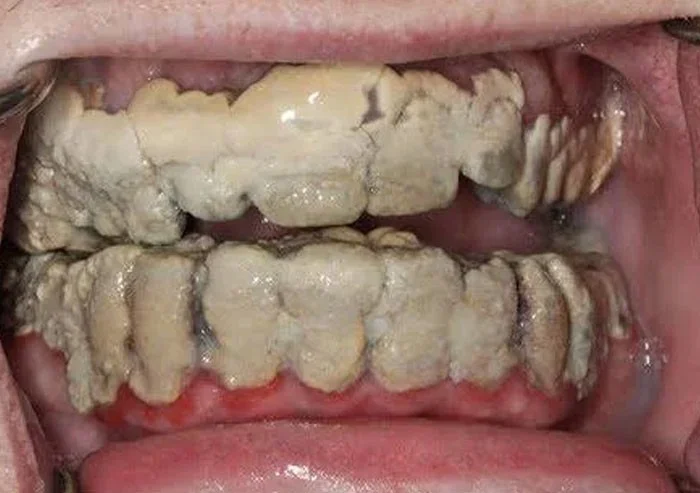

4. «Этот человек не чистил зубы 20 лет»